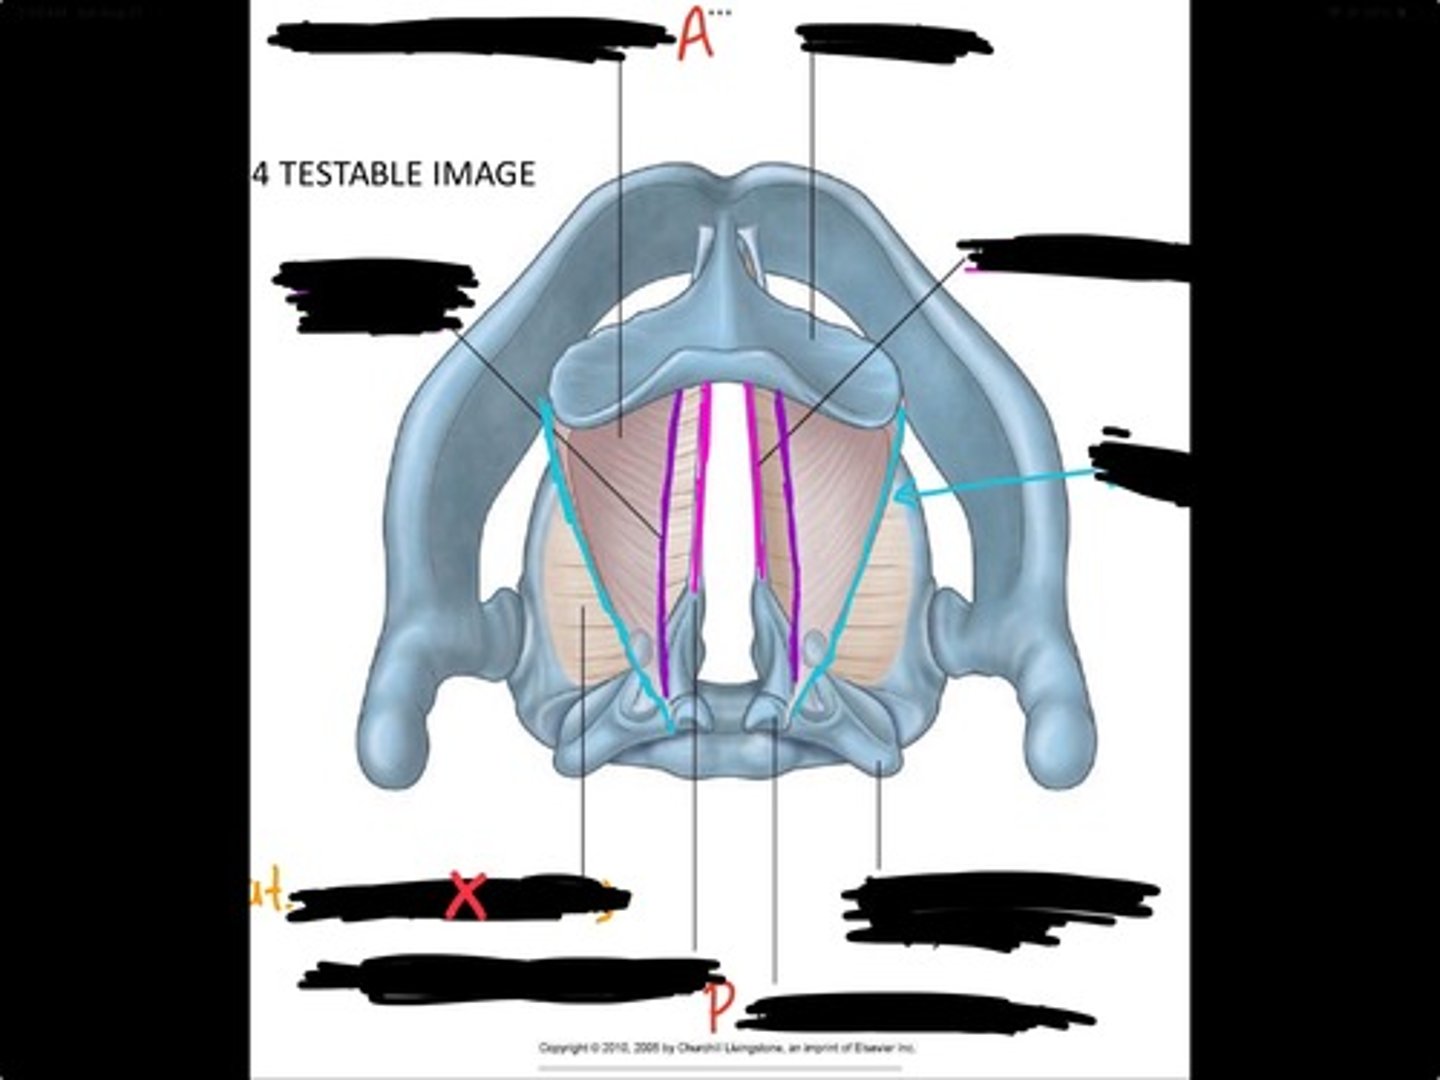

Vocal process of arytenoid

Conus elasticus

Vestibular ligament

Quadrangular membrane

Epiglottis

vocal ligament

Aryepiglottic ligament

Muscular process of arytenoid

Corniculate cartilage

Posterior crico arytenoid

oblique arytenoid

transverse artyenoid

Rima glottidis

Vocal ligament

Vocalis muscle

Lateral cricothyroid ligament

Lateral cricoartenoid